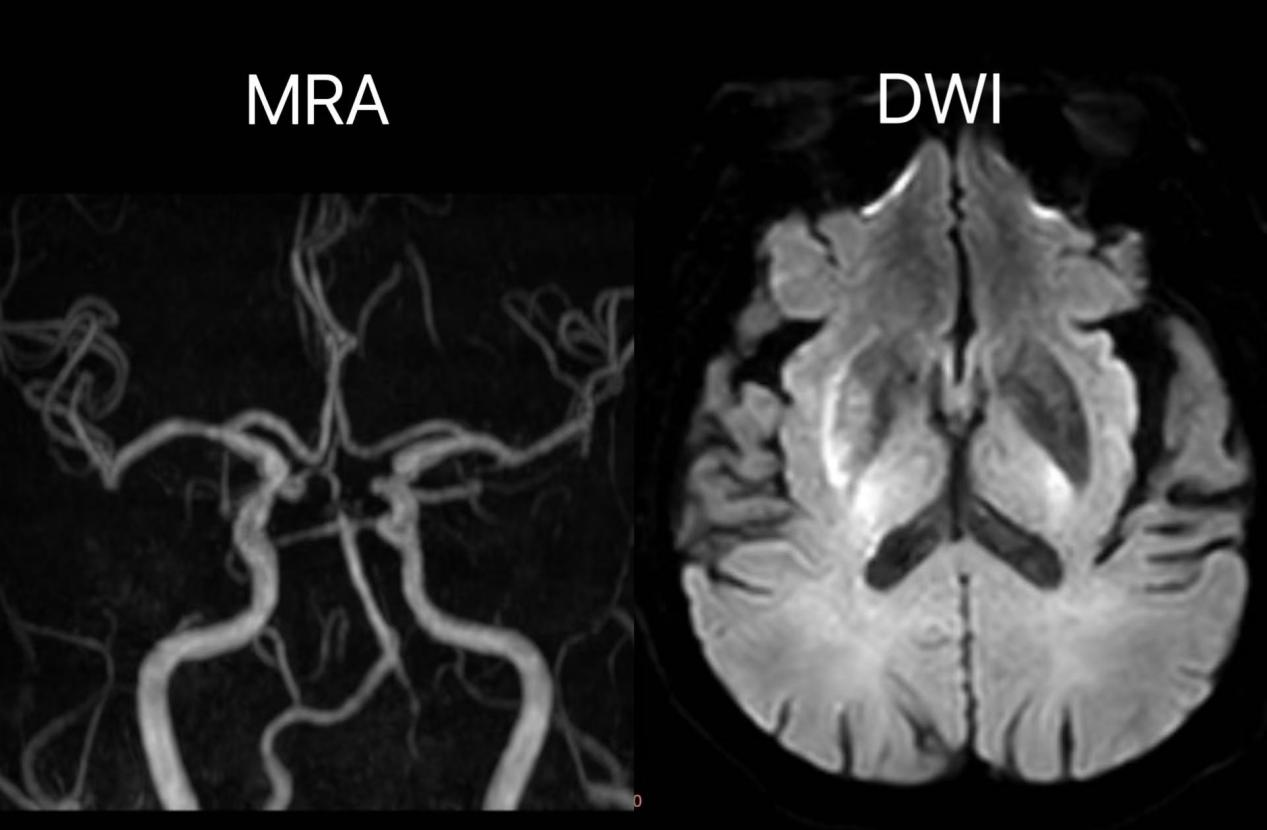

术后一天复查头颅MR示:右侧基底节区-放射冠少量斑片状急性期脑梗死灶;右侧大脑中动脉显影较前明显改善。